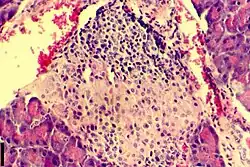

A histological image of an inflammatory infiltration of the islets of Langerhans of the pancreas

Insulitis is an inflammation of the islets of Langerhans, a collection of endocrine tissue located in the pancreas that helps regulate glucose levels, and is classified by specific targeting of immune cell (T and B lymphocytes, macrophages and dendritic cells) infiltration in the islets of Langerhans.[4][5][6][7] This immune cell infiltration can result in the destruction of insulin-producing beta cells of the islets, which plays a major role in the pathogenesis, the disease development, of type 1 and type 2 diabetes. Insulitis is present in 19% of individuals with type 1 diabetes and 28% of individuals with type 2 diabetes.[1][8][9] It is known that genetic and environmental factors contribute to insulitis initiation, however, the exact process that causes it is unknown.[10] Insulitis is often studied using the non-obese diabetic (NOD) mouse model of type 1 diabetes. The chemokine family of proteins may play a key role in promoting leukocytic infiltration into the pancreas prior to pancreatic beta-cell destruction.[11]